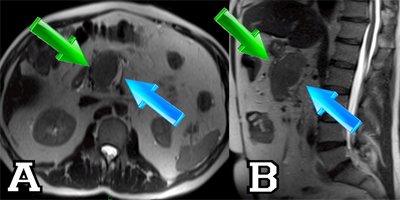

En la AngioRM se aprecia una dilatación aneurismática con trombo intraluminal en la vena mesentérica superior (VMS), esplénica y porta. Ver Figura nº2: AngioRM abdominal (al final del artículo).

Figura 3: AngioRM abdominal

AngioRM abdominal:

A: Secuencia Axial HASTE T2.

B: Secuencia Sagital HASTE T2. La flecha verde señala el trombo de la vena mesentérica superior (VMS). La flecha azul señala la luz permeable en la vena.